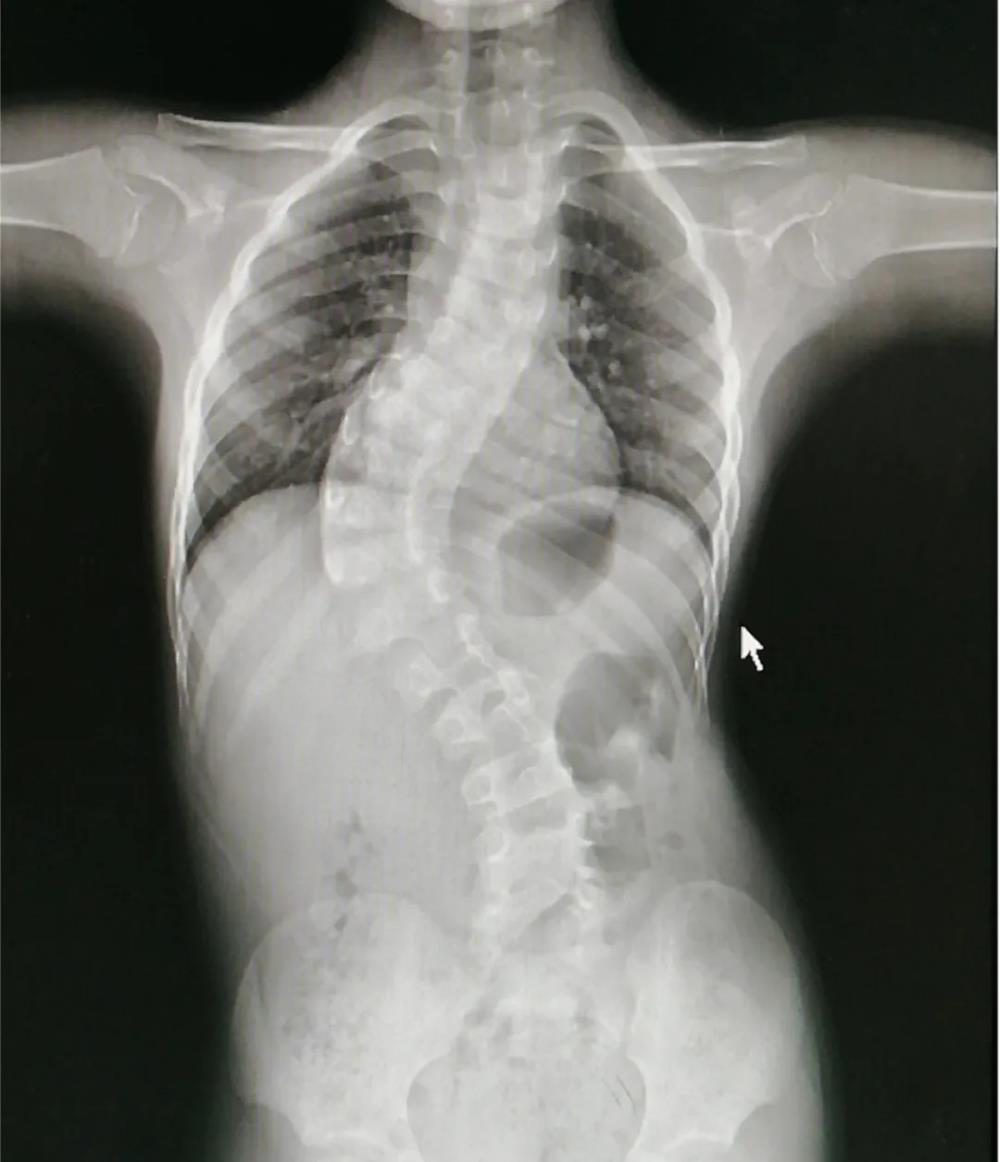

脊柱侧弯:又称脊柱侧凸,它是一种脊柱的三维畸形,包括矢状位、冠状位和轴位的序列异常。如果正位全脊柱X线片显示cobb角大于10°的侧方弯曲,即可诊断。

当Cobb角大于40°,可选择手术治疗

青少年特发性脊柱侧弯的手术指征:侧弯角度 >40° ,支具治疗无效,侧弯进展速度>5°/年和外观畸形明显者。手术治疗是通过钛合金或不锈钢螺钉和棒等内固定技术将弯曲的脊柱慢慢拉直固定,然后将移植骨覆盖于脊柱后方使弯曲的脊柱长在一 起,从而达到预防脊柱弯曲加重,改善心肺及消化功能的目的。